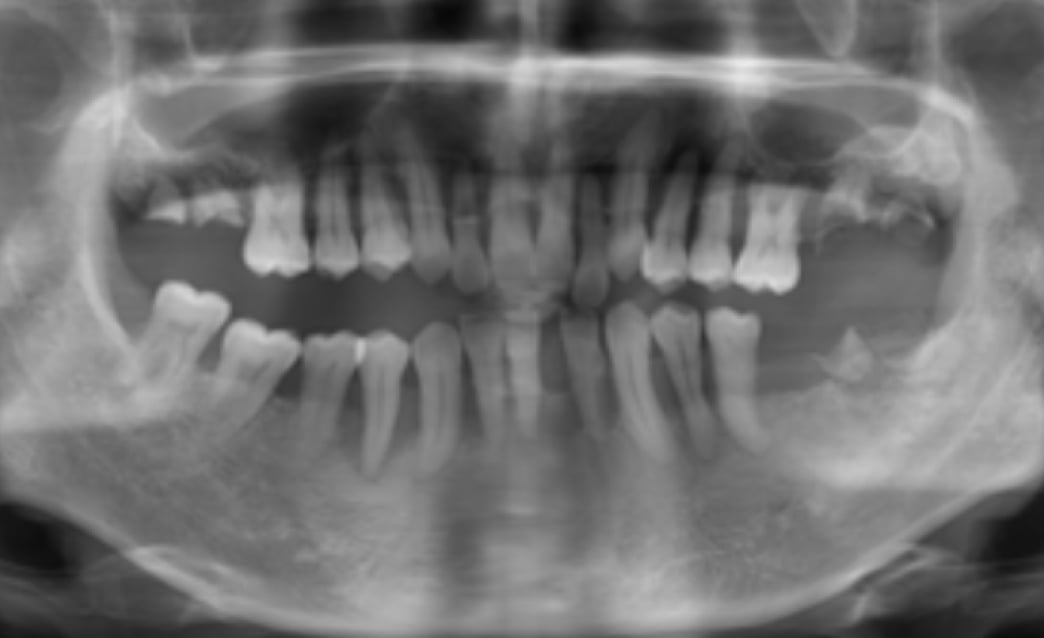

60代

Before

After

| 主訴 | 歯がぐらぐらする。 |

| 治療内容 | 下顎の残存歯は、歯周病が進行していたため全て抜歯をおこない、同日にインプラント埋入と仮歯の装着をしました。骨とインプラントが固定されるのを約3ヵ月待ち、型どりをして最終補綴を装着します。上顎にはフルデンチャーを使用し、快適に食事がとれています。 |

| 治療期間 | 6ヵ月 |

| 費用 | ¥3,586,000(税込み) |

| リスク・副作用 |

・外科処置が必要。コストがかかる。 |